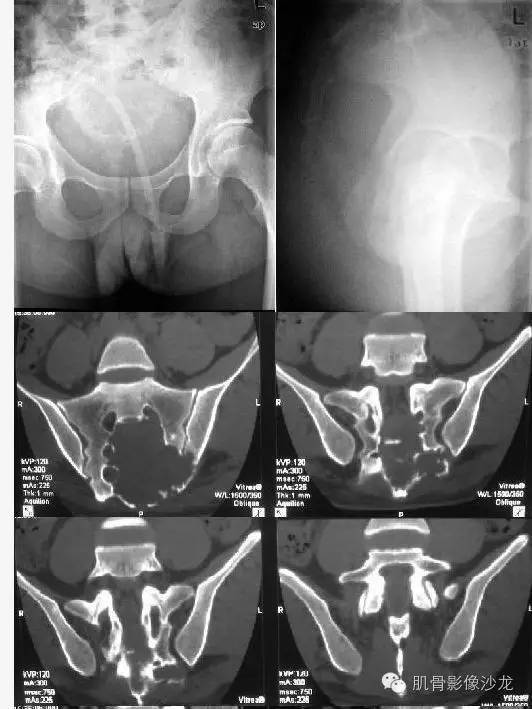

【病例】骶骨神经纤维瘤一例CT影像表现

首先定位,骶尾部骨质破坏,局部巨大软组织肿块,来源于骨?还是软组织病变?

骶骨膨胀性破坏,感觉骶恐扩大

从轴位像上看,病变起源于骶管内可能性大

明显膨胀,偏心,累及骶管骶孔

密度不均,有大范围低密度区

骶孔扩大,哑铃样生长,密度不均匀,强化不均匀强化

骶骨成受压改变

病史:32岁,男性,大小便困难2年,加重伴左侧腰骶部疼痛2个月。

病理:骶骨神经纤维瘤,细胞生长活跃伴局部细胞异型性。